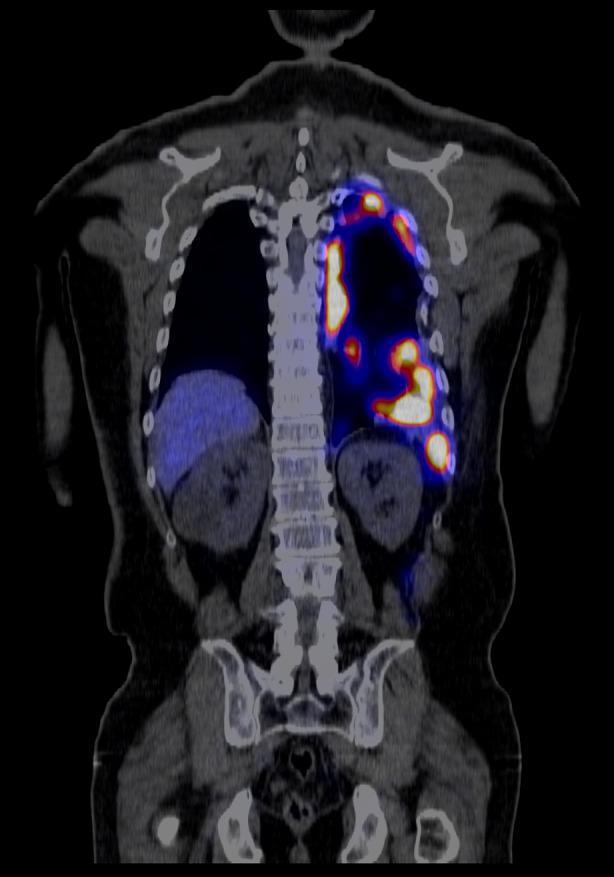

胸腔脾组织植入:精准医学可预防胸外科手术。

Thoracic splenosis: Precision medicine can prevent thoracic surgery.

Thoracic splenosis is a rare condition referring to the auto-transplantation of splenic tissue into the thoracic cavity following splenic trauma. We present a case of thoracic splenosis in a 62-year-old man who at the age of 17 suffered three gunshot wounds to the posterior thorax and abdomen, requiring a splenectomy and intercostal catheter insertion. In 2007, he underwent a thoracotomy and biopsy of a left sided pulmonary mass which was complicated by a haemothorax requiring an emergent return to theatre and rib resection to achieve haemostasis. The biopsy revealed granulation tissue. In 2023, Technetium-99m (Tc-99m) heat-damaged erythrocyte scintigraphy confirmed the diagnosis of thoracic splenosis. This case highlights the importance of recognizing this uncommon condition to prevent unnecessary investigation, as well as the use of Tc-99m heat-damaged erythrocyte scintigraphy to confirm the diagnosis.

摘要

胸腔脾组织自体移植是一种罕见的病症,指的是脾脏组织在脾脏创伤后自体移植到胸腔。我们报告一例62岁男性胸腔脾组织自体移植病例,该患者17岁时后胸部和腹部遭受三处枪伤,需要进行脾切除术和肋间导管插入术。2007年,他接受了开胸手术及左侧肺部肿块活检,术后并发血胸,需要紧急返回手术室并进行肋骨切除以止血。活检显示为肉芽组织。2023年,锝-99m(Tc-99m)热损伤红细胞闪烁扫描术确诊为胸腔脾组织自体移植。该病例凸显了认识这种罕见病症以避免不必要检查的重要性,以及利用Tc-99m热损伤红细胞闪烁扫描术来确诊的重要性。